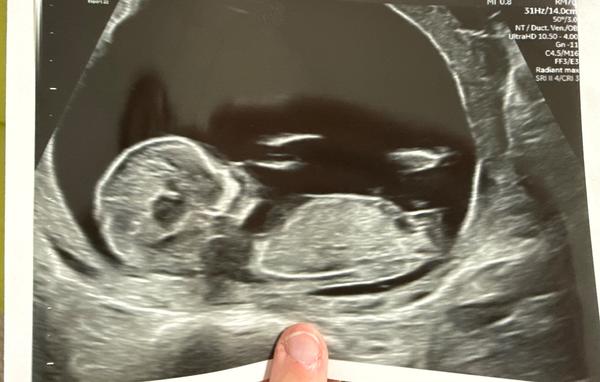

Ahojky pochlubte se svými fotografiemi z 1 screeningu? Ráda se podívám dozvěděli ste se už co čekáte?

@lujhu jestli narazis na tvoji fotku, tipuji holcicku, moje mala ve 13+2tt a na 90% holcicka

Jsem ted 30tt a uz se jen potvrzuje 🙂)